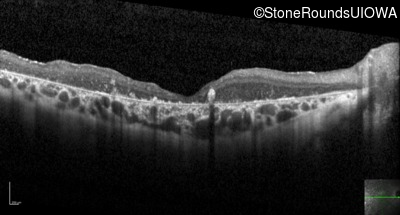

Optical Coherence Tomography - Right - 20/400 sc

Exemplar / OCT Stack